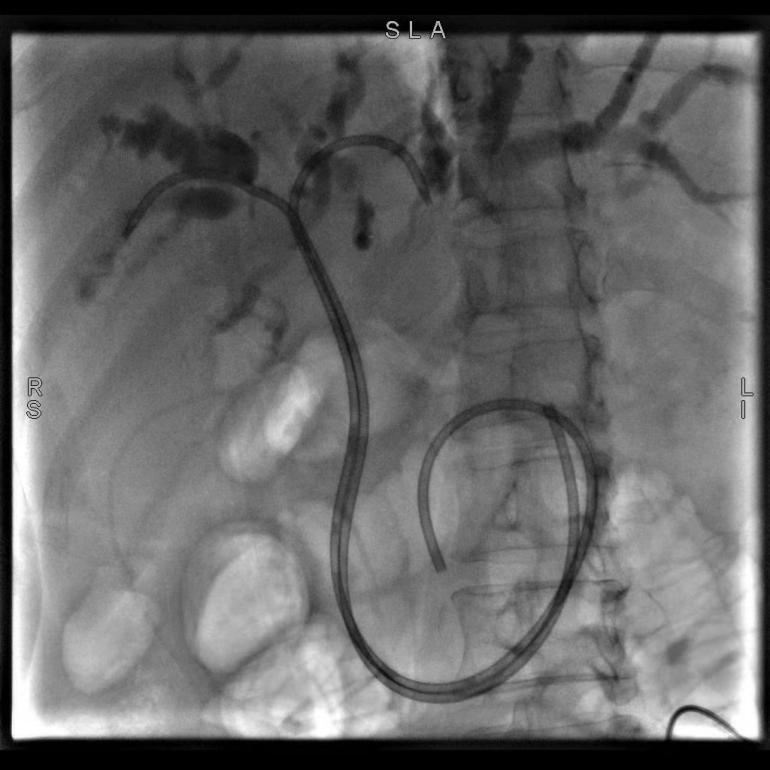

56歲的患者巫某,因“確診結腸癌伴肝轉移3年,皮膚鞏膜黃染1周”入院,完善檢查后,診斷為梗阻性黃疸、肝繼發惡性腫瘤。陶銳主任醫師組織團隊在討論了巫女士的病情后,決定實施ERCP+EST+ERBD術,術中主刀陶銳主任醫師根據患者的病情置入了鼻膽管改良塑料支架,患者術后引流通暢,梗阻情況明顯好轉。

(圖示為置入鼻膽管改良塑料支架)